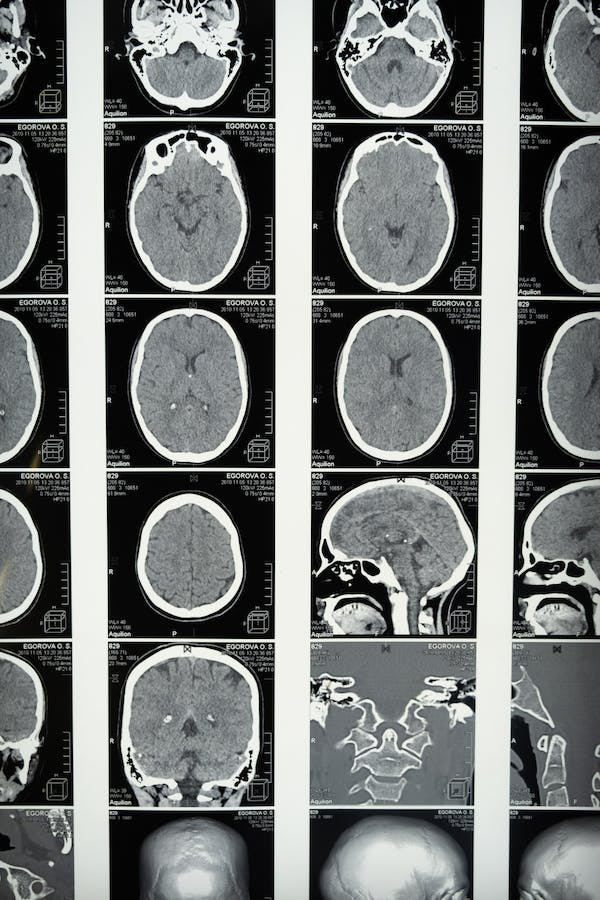

Los estudios de imágenes cerebrales sugieren que la obesidad se asocia con atrofia neural. Se han informado alteraciones estructurales en la arquitectura neural de personas con obesidad. Por ejemplo, un índice de masa corporal elevado se relaciona con una disminución del volumen cerebral, independientemente de la edad y las comorbilidades. Además, un IMC elevado está asociado con la atrofia de la materia gris en las regiones temporales, frontales y occipitales.

En adición, se presentan efectos similares en el hipocampo, el tálamo y el mesencéfalo. No menos importante, se ha documentado una disminución de la integridad de la materia blanca en todo el cerebro.

Además de las alteraciones estructurales y morfológicas en el cerebro de las personas con obesidad, los estudios de imágenes cerebrales muestran una actividad funcional alterada. Lo anterior incluye una disminución del flujo sanguíneo regional hacia la corteza prefrontal en adultos sanos con un IMC elevado.

También, se ha observado una reducción significativa de la actividad funcional en áreas corticales asociadas con la memoria episódica, como el giro angular y la corteza prefrontal dorsolateral, en personas con obesidad y resistencia a la insulina. Así, las personas con obesidad muestran una menor activación relacionada con tareas de memoria de trabajo en la corteza parietal derecha (Dye et al., 2017).

La obesidad se asocia con un aumento de la “edad cerebral” en lo que respecta a la atrofia de la materia blanca cerebral. La mayor atrofia se identifica en la mediana edad, lo que equivale a un aumento estimado de 10 años en la edad cerebral.